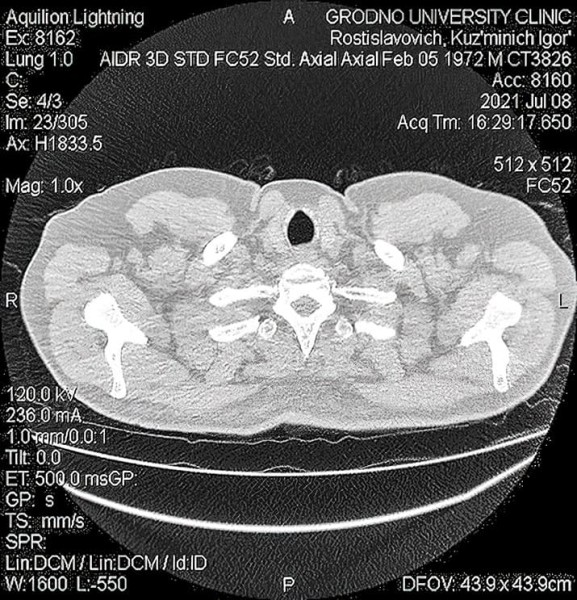

• COVID-ассоциированный инвазивный легочный аспергиллез: проблемы диагностики и лечения